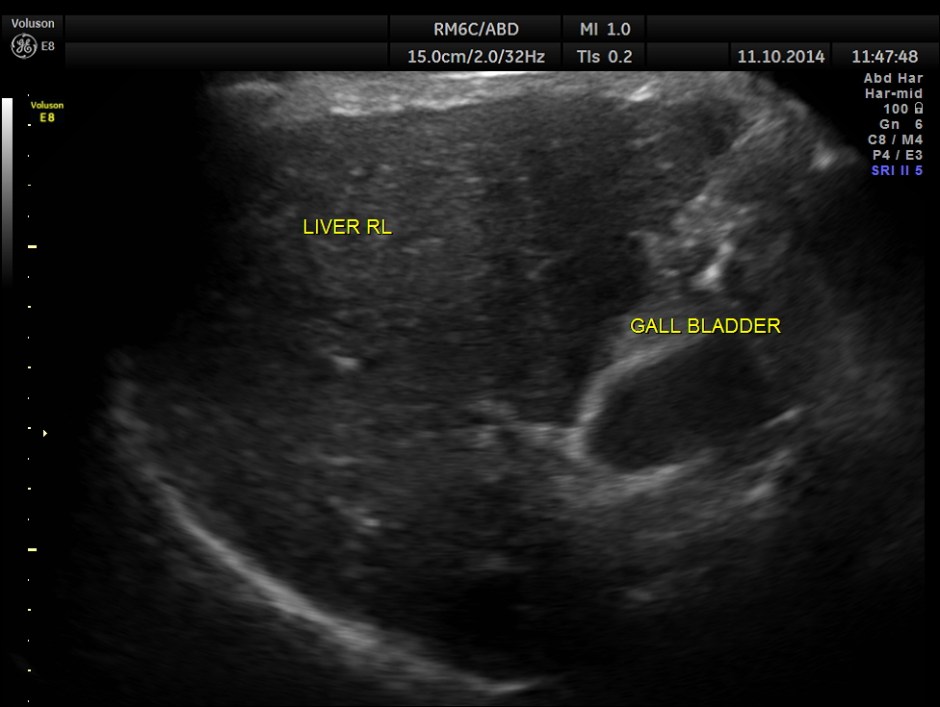

This was a 50 year old gentleman with history of occasional alcohol intake and complaints of tiredness and fatigue.

His ultrasound showed the following features.

Liver texture is coarse ; Portal vein appears to be shrunk.